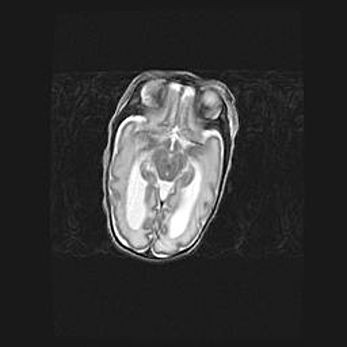

Церебральная ишемия II.

Возраст: 5 дней

Вес: 3400 г

Пол: женский

Окружность головы: 35 см

Срок гестации: 39 недель

Церебральная ишемия – это заболевание, характеризующееся недостаточностью (гипоксией) либо полным прекращением (аноксией) снабжения мозга кислородом по причине закупорки одного или нескольких сосудов. Это приводит к  что метаболическим расстройствам различной степени тяжести в тканях головного мозга, развитию коагуляционных некрозов и гибели нейронов.